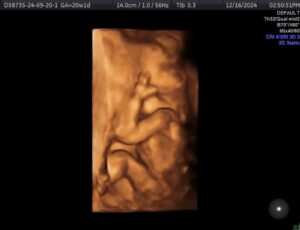

I had my tubal ligation reversal surgery on 4/29/24 and we found out we were pregnant August 21st at 7dpo.

We are amazed with the side effects of post tubal ligation syndrome being reversed and to get pregnant in four cycles.

I’m currently 21 weeks pregnant and he’s thriving!